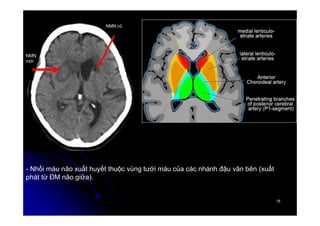

** Các nhánh động mạch đậu – vân:

1. Các động mạch đậu vân trong xuất phát từ ĐM não trước.

2. Các nhánh đậu vân ngoài xuất phát từ động mạch não giữa.

- Nhồi máu não xuất huyết thuộc vùng tưới máu của các nhánh đậu vân bên (xuất

phát từ ĐM não giữa).